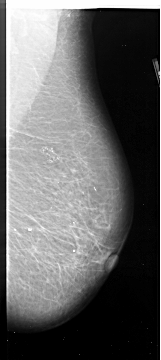

A_1088_1.LEFT_CC

LEFT_CC LINES 5896 PIXELS_PER_LINE 2911 BITS_PER_PIXEL 16 RESOLUTION 42 OVERLAY

FILE: A_1088_1.LEFT_CC.OVERLAY

TOTAL_ABNORMALITIES 1

ABNORMALITY 1

LESION_TYPE CALCIFICATION TYPE PLEOMORPHIC DISTRIBUTION SEGMENTAL

ASSESSMENT 4

SUBTLETY 3

PATHOLOGY MALIGNANT

TOTAL_OUTLINES 1

BOUNDARY